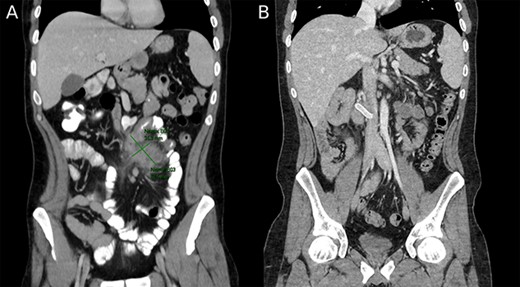

Two months prior to surgery and before initiating CD treatment, the patient was hospitalized. A computed tomography (CT) demonstrated a 30-cm region of marked thickening in the terminal ileum, an adjacent multilocular abscess measuring 4.3 × 3 × 2.5 cm and intestinal malrotation. The patient was managed conservatively with antibiotics and total parenteral nutrition (TPN). Drainage could not be performed due to the abscess location.

A follow up colonoscopy performed 1 month after antibiotic treatment demonstrated cobblestone mucosa along with a severe stenosis in the terminal ileum and a small bowel fistula. In addition, an abdominal CT showed a 10-cm section of bowel wall thickening in the terminal ileum and remnants of the abscess (Fig. 3). Ileocecectomy was electively planned due to the severity of disease and persistence of symptoms.

(A) Preoperative image depicting intestinal malrotation and an abdominal abscess measuring 62.5 × 35.3 mm. (B) Postoperative image depicting a Gore-tex graft between the superior mesenteric vein and inferior vena cava.